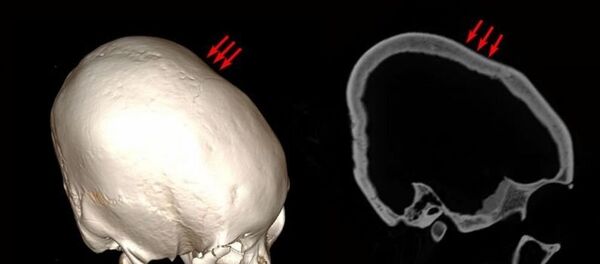

据《每日邮报》报道,维也纳大学专家对克罗地亚奥西耶克市考古遗址2013年出土的少年(12至16岁)遗骸进行了研究。

专家提取了遗骸的DNA样本,确定了其具体来历,并发现遗骸头骨呈现不寻常的

圆锥状

。

这些遗骸可以追溯到公元415至560年。专家认为,头骨变形可能与文化认同和当地习俗有关。

人们是通过在头部固定木板,借助绷带和特殊头饰使头骨变成圆锥状。相关研究结果发表在《PLOS One》杂志上。